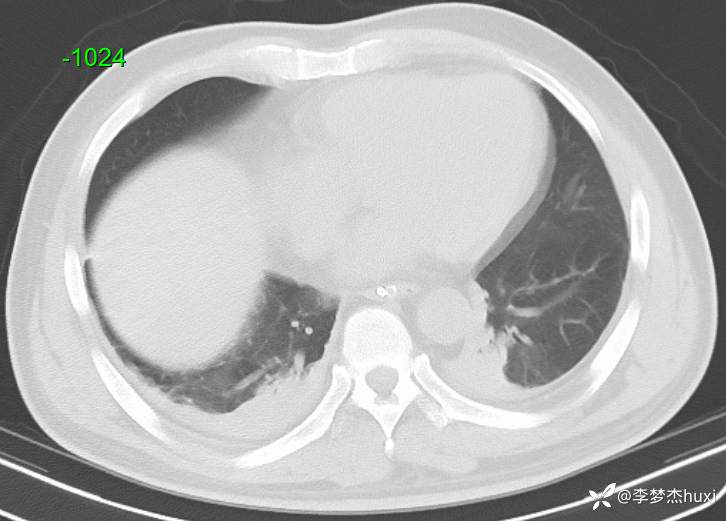

【现病史及既往史】: 1.现病史:患者老年 男,于入院前1天,患者在骑自行车时发生车祸,致伤头部,右颞顶部受力,伤后患者意识不清,右侧外耳道及右侧鼻腔出血,院外未处理,急来我院急诊就诊,查头颅CT示:右侧额颞顶枕部硬膜下血肿,颅内积气,蛛网膜下腔出血,左侧额颞部硬膜下出血?脑干密度减低,右侧颞顶部头皮软组织肿胀,右侧颞、顶骨骨折,右侧乳突小房密度增高。右侧外耳道密度增高。右侧蝶窦密度增高。胸部CT+三维重建示:双肺索条,双肺透过度欠均匀,双肺纹理增重,主动脉钙化,冠状动脉钙化。急诊以“闭合性颅脑损伤重型”收入我科。

【治疗经过及结果】:辅助检查:查头颅CT示:右侧额颞顶枕部硬膜下血肿,颅内积气,蛛网膜下腔出血,左侧额颞部硬膜下出血?脑干密度减低,右侧颞顶部头皮软组织肿胀,右侧颞、顶骨骨折,右侧乳突小房密度增高。右侧外耳道密度增高。右侧蝶窦密度增高。胸部CT+三维重建示:双肺索条,双肺透过度欠均匀,双肺纹理增重,主动脉钙化,冠状动脉钙化。

入院发生肺炎,猜病原菌